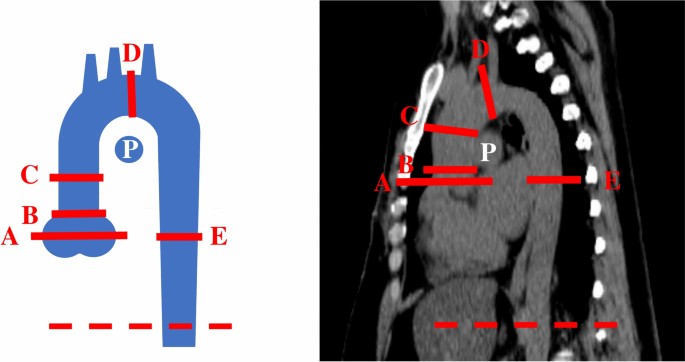

One reader (A.L.) measured the thoracic aortic diameters on the hospital’s Picture Archiving and Communication Systems (PACS; Sectra vs. 24.2.). Multiplanar reconstruction (MPR) of the image stacks were used to allow three-dimensional presentation of the structures. The thoracic aortic diameters were measured from the following segments: the sinus of Valsalva, sinotubular junction, tubular part, mid-aortic arch, and mid-descending (thoracic) aorta (DA; Fig. 1)4. The reader measured two perpendicular measurements from these segments, the other representing the maximum diameter. Measurements were obtained by drawing lines from the outer-to-outer vascular wall, vertical to the centerline of the vessel3. Next, the maximum diameter of the aorta was used for statistical analyses. The thoracic aorta was considered dilated if its greatest dimension was > 40 mm in any of the measured planes3. Lastly, AHI and ASI determination and results are presented and discussed in the Supplementary Materials.

A schematic presentation of the thoracic measurement segments (left) and a sagittal view image (right). A: sinus of Valsalva, B: sinotubular junction, C: tubular part, D: mid-aortic arch, E: mid-descending (thoracic) aorta, P: right pulmonary artery. The dashed line indicates the level of the diaphragm.